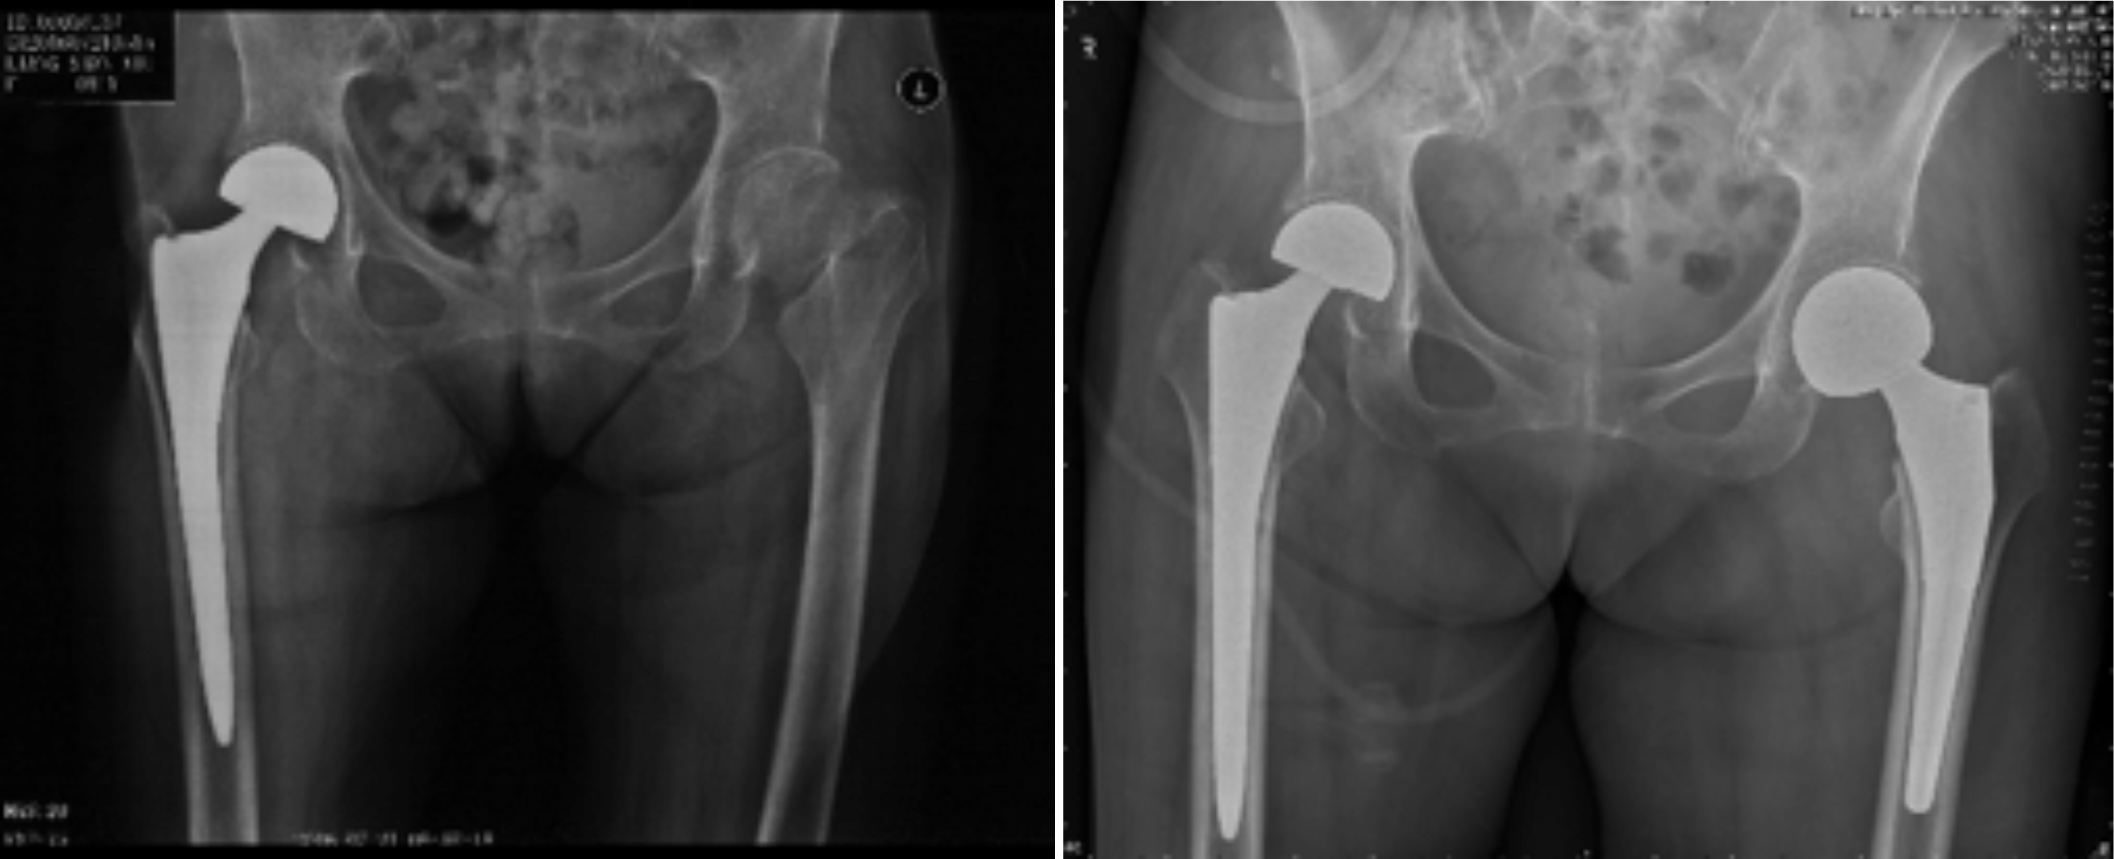

一、人工关节置换 各种晚期骨关节病的关节置换手术治疗是北京清华长庚医院关节外科中心的一大特色,包括股骨头坏死、髋膝骨关节炎、类风湿关节炎、强直性脊柱炎、髋关节发育不良、关节强直、超过80岁的超高龄股骨颈骨折患者的关节置换手术等,我中心在人工关节初次置换及翻修上作了大量工作,置换的难度和手术效果方面已达到国际先进水平,导航下全膝关节置换术:大大提高膝关节置换手术的精确度。

股骨头缺血性坏死

髋关节发育不良

强直性脊柱炎双髋强直

股骨颈骨折